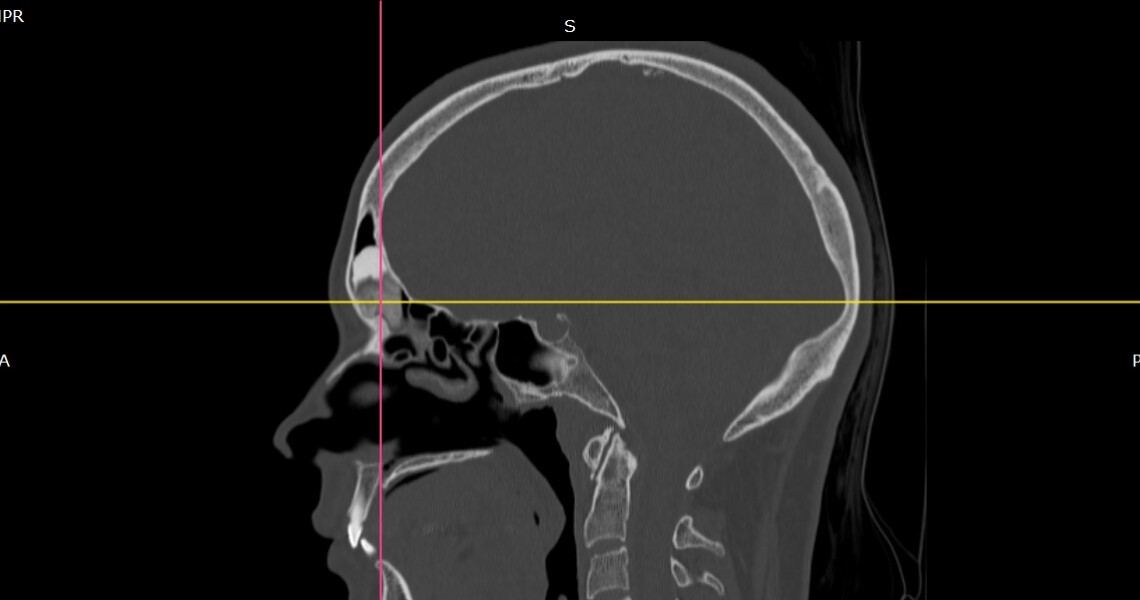

У ЛОР-відділенні КП «Полтавська обласна клінічна лікарня ім. М.В. Скліфосовського» було вперше видалено остеому лобної пазухи гігантських розмірів ендоназальним доступом.

Пацієнтка перебувала під спостереженням завідувача кафедри оториноларингології з офтальмологією, к.мед.н Безеги Михайла, який особисто виконав операцію. Хірургічне втручання тривалістю понад 4 години включало полісинусотомію з корекцією внутрішньо-носових структур та видалення остеоми. Післяопераційний період пройшов без ускладнень. Уже на шостий день після операції пацієнтку виписано зі стаціонару у задовільному стані.

For the first time, a giant frontal sinus osteoma was removed endonasally in the ENT Department of the Municipal Enterprise “M. V. Sklifosovsky Poltava Regional Clinical Hospital.”

The patient was under the supervision of Associate Professor Mykhailo Bezeha, PhD in Medicine, Head of the Department of Otorhinolaryngology with Ophthalmology, who personally performed the surgery. The operation, which lasted more than four hours, included a polysinustomy with correction of intranasal structures and removal of the osteoma. The postoperative period passed without complications. On the sixth day after the surgery, the patient was discharged from the hospital in satisfactory condition.